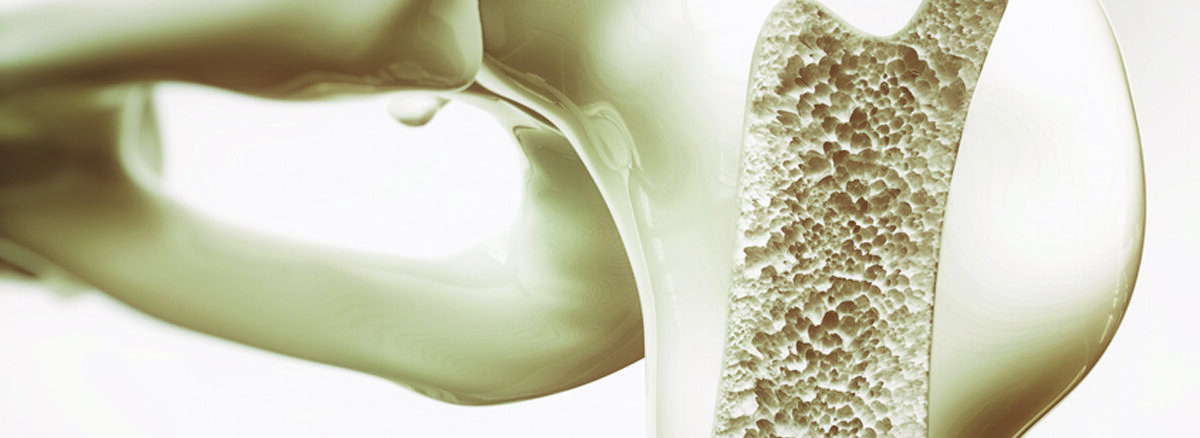

Osteoporoz, halk arasında bilinen adıyla kemik erimesi, kemiklerin incelmesi ve zayıflaması ile karakterize edilen bir hastalıktır. Bu hastalık, genellikle kemik yoğunluğunun azalması ve kemik yapısının bozulması ile kendini gösterir. Osteoporoz, zamanla kemikleri kırılgan hale getirerek, ani bir düşme ya da basit bir çarpma sonucu bile kırıklara yol açabilir. Özellikle menopoz dönemi sonrası kadınlarda daha yaygın görülse de, her yaşta ve her cinsiyette osteoporoz riski bulunmaktadır.

Osteoporoz, kemiklerin zayıflaması ve kırılgan hale gelmesi durumudur. Normalde kemikler, sürekli olarak yenilenen bir yapıya sahiptir. Kemik yapısının güçlenmesi ve yenilenmesi için kalsiyum, fosfor, D vitamini ve diğer mineraller gereklidir. Ancak osteoporozda, kemiklerdeki mineral yoğunluğu azalır, bu da kemiklerin zayıflamasına yol açar. Kişi, kemiklerinde herhangi bir travma olmadan da kırıklarla karşılaşabilir.